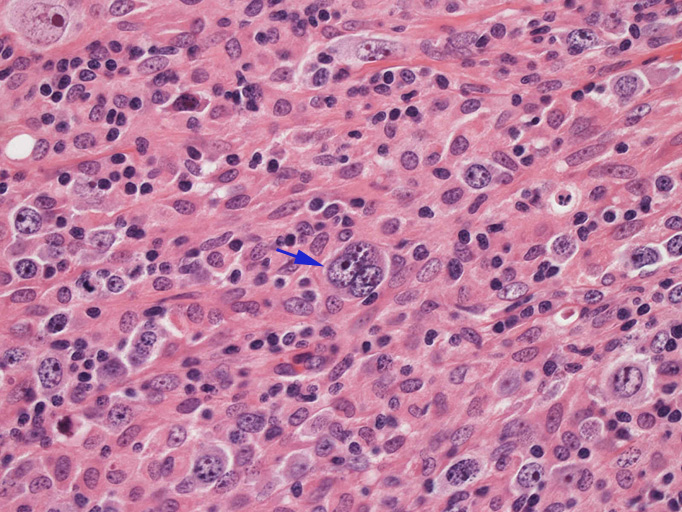

結節構造内では, 好酸性細胞質をもつ組織球の増生を背景に大型異型細胞が散在性または集蔟して増殖している。被膜下にも線維化組織内にbizzarreな大型細胞が認められる。リンパ球は小型リンパ球が大型異型細胞を含む組織球性の結節辺縁に存在する。大型細胞は, centroblastic cellが多く, その他 Hodgkin cell-like cell, RS細胞様巨細胞, 腎臓型の核をもった細胞, 多型核の細胞など多彩な形態を示す。異型核分裂像をふくむ核分裂像が多い。

大型異型細胞の形態